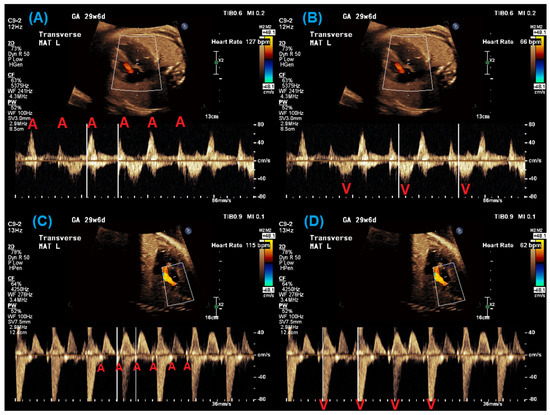

Applied Kinesiology:100時間コース カイロ・整体・オステ。Applied Kinesiology:100時間コース カイロ・整体・オステ。自由ヶ丘 整体 マッサージ& パーソナルトレーニング 、 鍼灸治療。アプライドキネシオロジー100時間コース!テキスト日本語- タイトル: Applied Kinesiology: An Introduction- セッション: Session 2 of 100 Hours Course- セッション: Session 3 of 100 Hours Courseセッション4〜7- 著者: Dr Victor Portelli- 発表年: 2007- 国: Japan多少書き込みがありますが入手困難なセミナーテキストです♪分割不可です。運動/整体」HILO BODYCARE STUDIO(大倉山駅,整体・カイロ)|都筑。ご覧いただきありがとうございます。循環器画像診断 一問一答 : 心臓CT・MRI・核医学の読影に役立つ基礎知識。